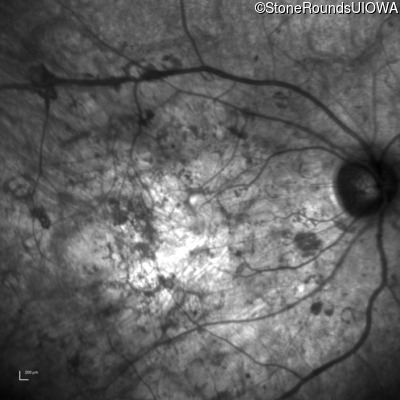

Infrared Fundus Photograph - Right - Hand Motion sc

Exemplar